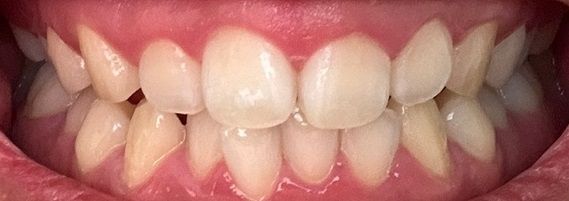

치아교정 해야될까요? 사랑니는 어떻게 해야할까요?

가족력은 아버지가 치열이 고르고 충치가 없고, 어머니는 치열이 고르지 않고 충치가 많습니다.

동생도 치열이 고르지 않고 충치는 없습니다.

치아교정을 생각하게 된 계기는 지인의 권유인데, 교정을 받아도 괜찮을지 궁금합니다.

사진상으로 보면 치열등에 크게 문제가 잇어 보이진 않습니다. 교정은 환자분의 선택하시면될것같고, 사랑니 발치 여부도 교정진단을 먼저 받아보시는게 좋을것같습니다.